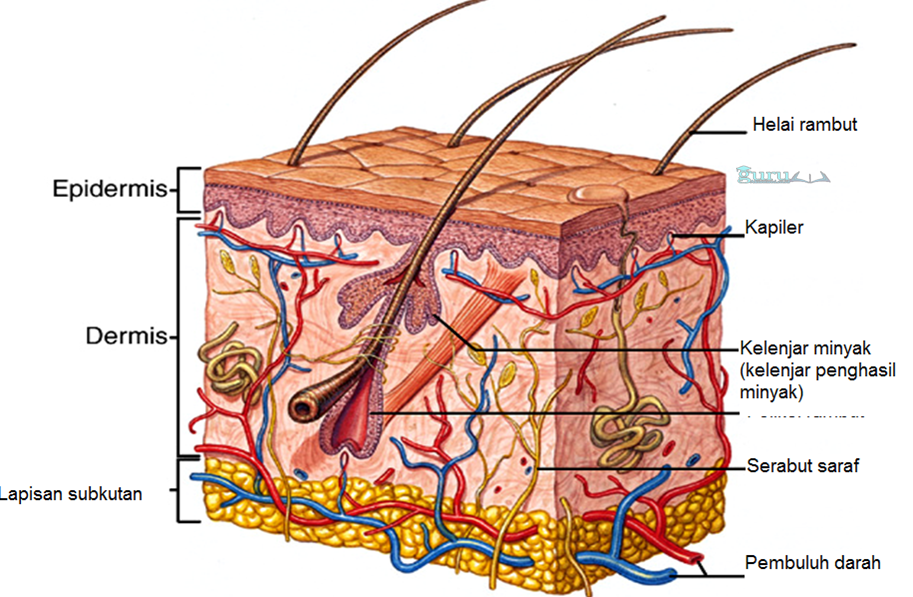

1. Kulit

Kulit merupakan adanya sebuah lapisan sebagai pelindung terluar yang ada di suatu permukaan tubuh. Kulit terkandung dalam organ ekskretoris karena dapat menghilangkan suatu residu dalam bentuk kelenjar keringat.

Kulit tidak hanya organ ekskretoris, tetapi berfungsi untuk indera peraba dan indera perasa. Kulit yakni terdiri dari 3 jenis lapisan, yang masing-masing memiliki sebuah fungsi masing-masing, diantaranya ialah sebagai berikut:

a. Epidermis (Lapisan Kulit Ari)

Epidermis merupakan sebuah lapisan kulit terluar dan sangat tipis. Epidermis yakni terdiri atas beberapa lapisan Malphigi dan lapisan tanduk. Lapisan terangsang terdiri dari sel-sel mati yang mudah diangkat dan tidak mengandung pembuluh darah dan serabut saraf, hingga lapisan tersebut tidak bisa berdarah saat dikupas.

b. Dermis (Lapisan Kulit Jangat)

Dermis merupakan suatu lapisan kulit yang memiliki letak di bagian bawah lapisan epidermis. Lapisan dermis tersebut yakni lebih tebal dari pada lapisan epidermis tersebut.

c. Jaringan Ikat Bawah Kulit

Lapisan tersebut yakni memiliki letak di bagian bawah dermis, antara lapisan jaringan ikat di bagian bawah kulit terhadap dermisyang telah dibatasi dengan sebuah sel-sel lemak. Dan lemak memiliki fungsi sebagai melindungi tubuh dari benturan serta sumber energi dan penghalang terhadap suhu dalam tubuh.